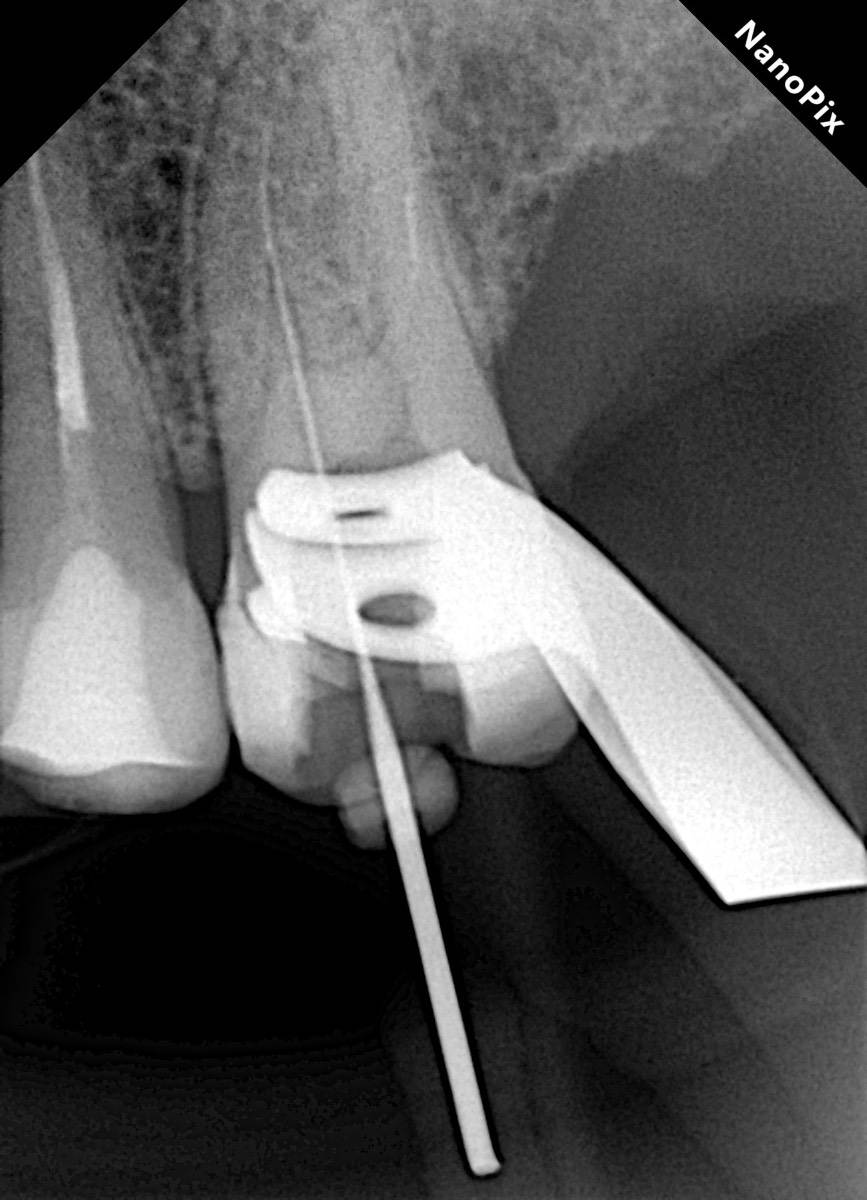

Гарриевич Опубликовано 31 января Автор Поделиться Опубликовано 31 января Когда в твоем кресле оказывается пациент с редким заболеванием «стоматолог-терапевт» работать всегда… легче. Именно! Потому что ты на 100% уверен, что этот человек понимает разницу между «гарантия» и «прогноз», а он на 100% уверен, что ты тот кто ему нужен. Зуб 4.7 со сложной анатомией, ступенькой в мезиальной системе, двойным изгибом, пропущенным каналом и апикальным периодонтитом. Реколл 1 год И сам осмотр через 1 год 4 1 1 Ссылка на комментарий

Гарриевич Опубликовано 2 февраля Автор Поделиться Опубликовано 2 февраля @Carioznik да, им проще сглаживать ступень, проходить длинные каналы, в дистальном отделе удобнее фиксировать файл 1 1 Ссылка на комментарий